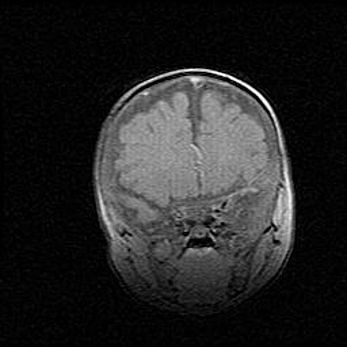

Церебральная ишемия II.

Возраст: 7 дней

Вес: 3350 г

Пол: женский

Окружность головы: 35 см

Срок гестации: 39 недель

Ишемия головного мозга – это состояние, которое развивается в ответ на кислородное голодание вследствие недостаточного мозгового кровообращения. У новорожденных она является следствием дефицита кислорода, что ведет к метаболическим расстройствам различной степени тяжести в тканях головного мозга, в том числе к развитию коагуляционных некрозов и гибели нейронов.